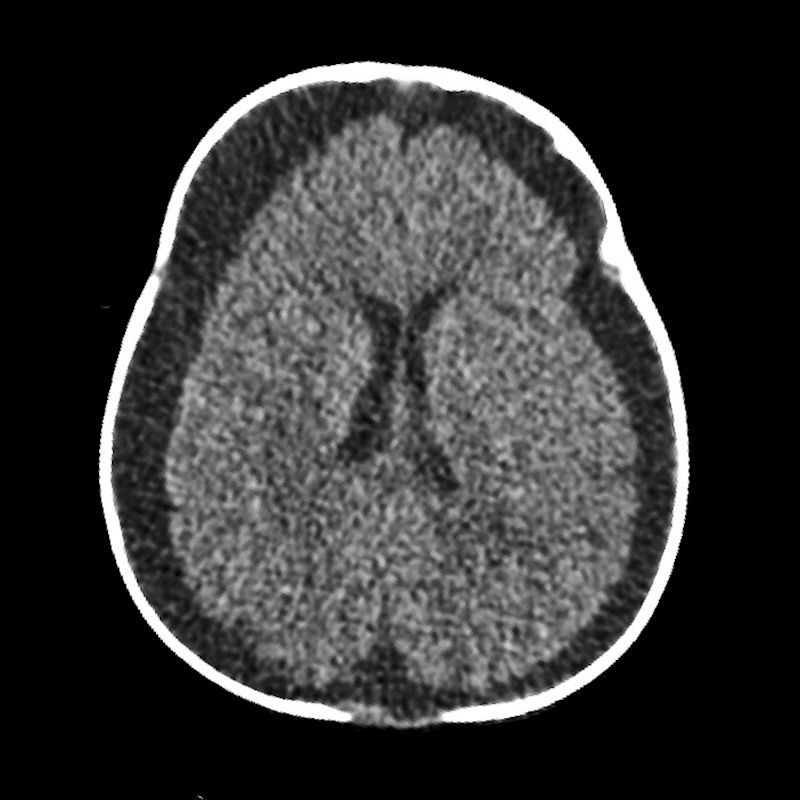

- E) Subdural hematohigroma ile uyumlu yoğun içerikli bileşenler

- F) Verteks düzeyinde lolipop/iribaş (tadpole) işareti

- G) Verteks düzeyinde köprü ven trombozuna/yaralanmasına ait duyarlılık artefaktı

- Köprü ven trombozu: Manyetik duyarlılık görüntülemede, kortikal ven trasesinde duyarlılık artefaktı olarak ya da “lolipop” ve “iribaş” (tadpole) işareti şeklinde görülür. Vakaların yaklaşık %30-45’inde saptanır.